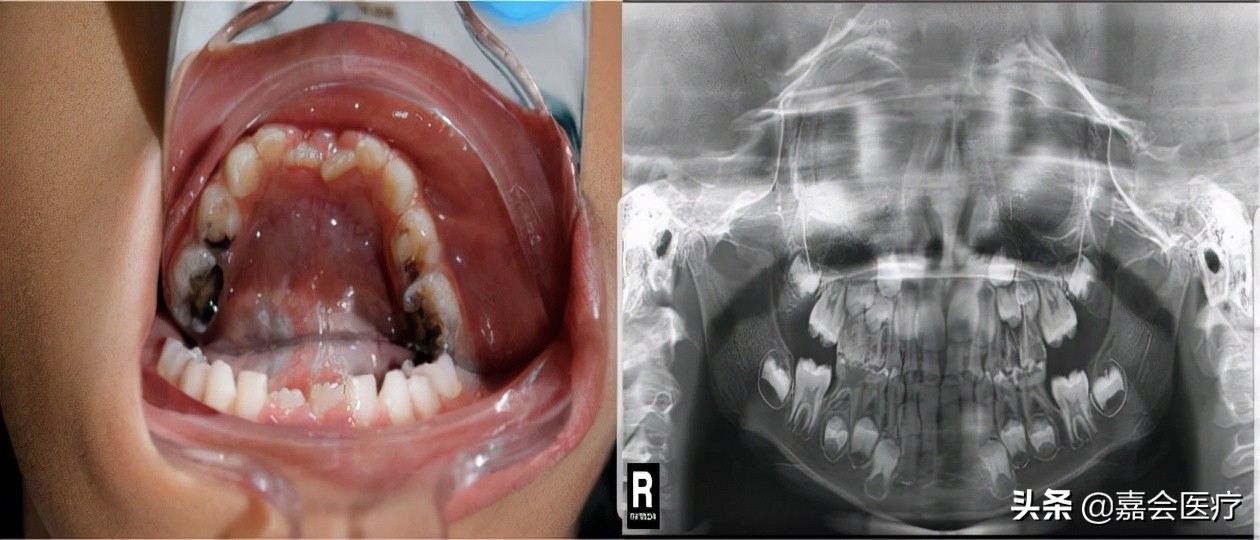

(2)口腔检查:可见患儿有口唇干燥、多发龋齿和腮腺肿大并压痛,舌部有念珠菌感染征象,伴吞咽困难。外阴检查示红肿和抓痕。

图1. 口腔检查和X线口腔全景片:多发龋齿,舌部念珠菌感染[1]